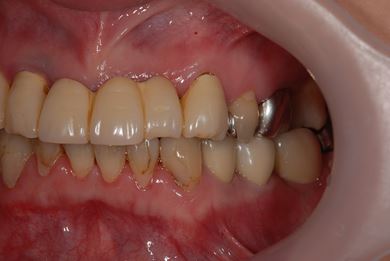

| カテゴリー | 【インプラント治療】【セラミック治療】 | ||||||||||||||||||||||||||||||||

| 性別/年齢 | 女性 / 40歳 | ||||||||||||||||||||||||||||||||

| 主訴 | 右下のブリッジが外れているかもしれないという診断を受けましたが、開けてみないとわからない、場合によっては部分入れ歯と言われ、セカンドオピニオンを希望。腫れがあるのも気になります。 | ||||||||||||||||||||||||||||||||

| 治療方針 | 右下奥、骨再生法によりインプラント治療を可能にする。 | ||||||||||||||||||||||||||||||||

| 治療内容 | インプラント3本(GBR、テンポラリーインプラント+仮歯)、ハイブリッドセラミックブリッジ3本、ハイブリッドセラミッククラウン2本 | ||||||||||||||||||||||||||||||||

| 総治療費 | 1,524,338円 | ||||||||||||||||||||||||||||||||

| 治療期間 | 1年0ヶ月 |